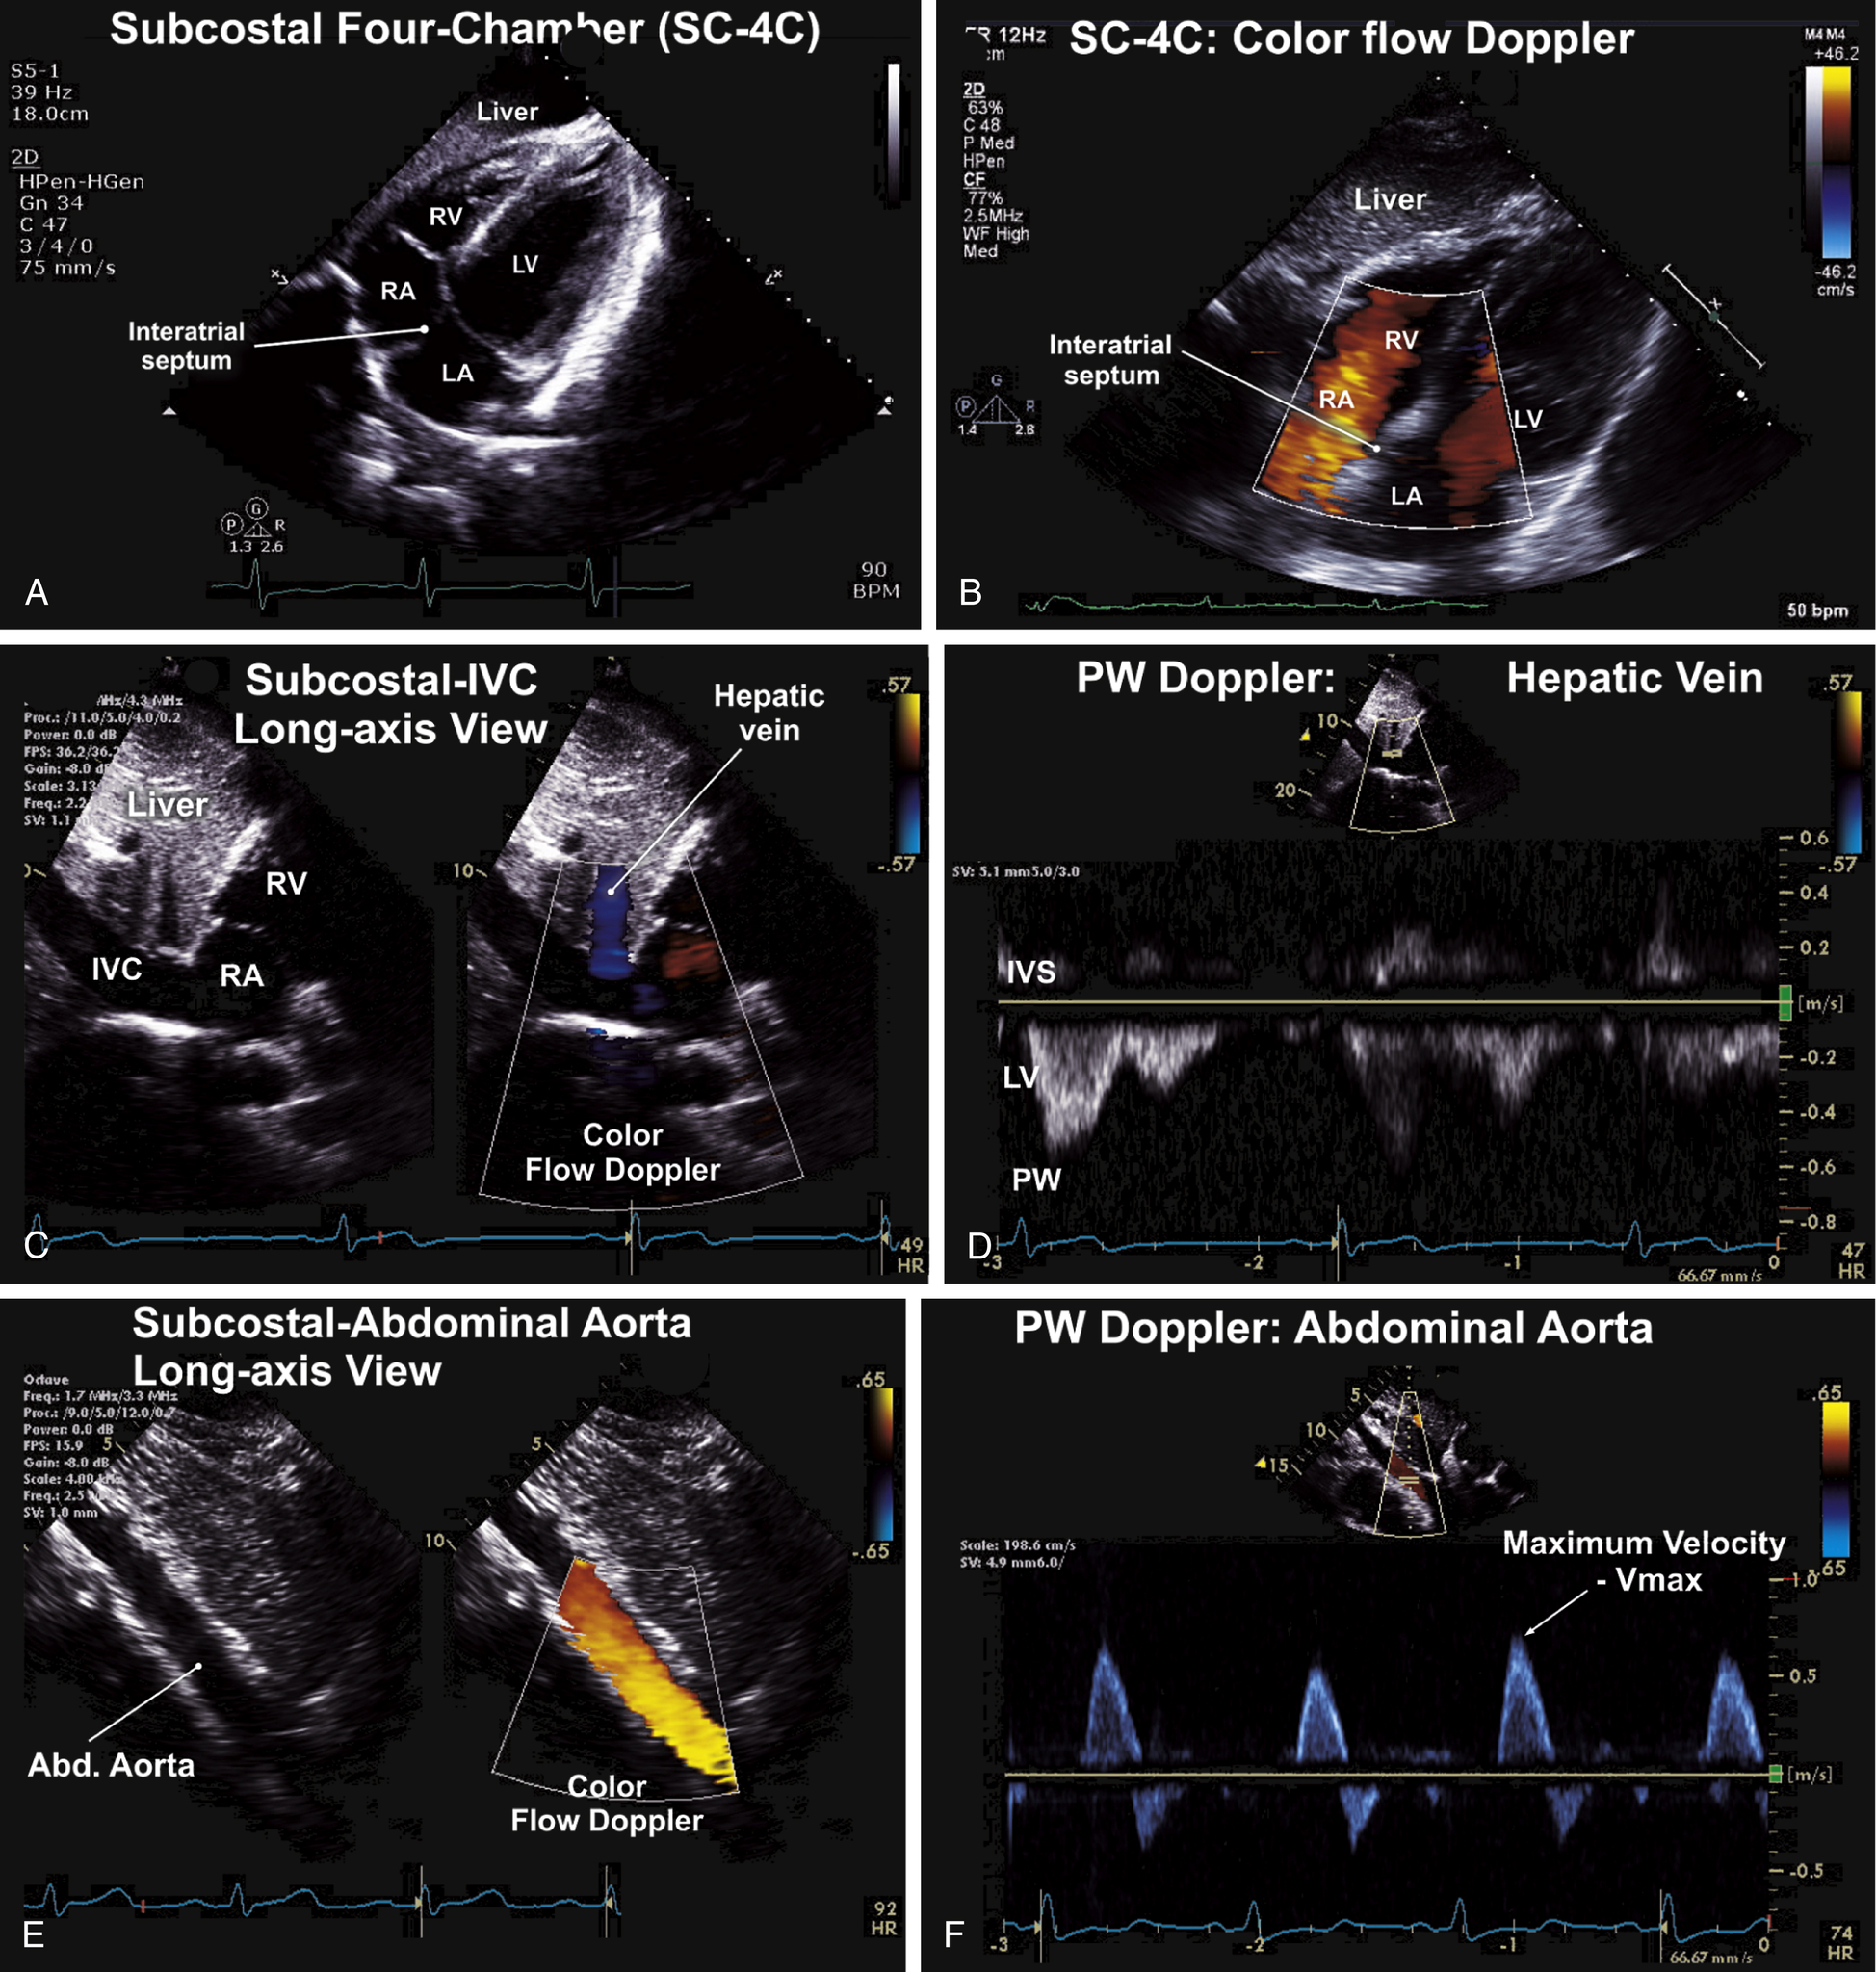

Subcostal Views (see Fig. 9.9)

| Subcostal Views (see Fig. 9.9) | ||

| Subcostal (SC) | Four-chamber | IAS, LV, RV, LA, RA, MV, TV |

| SC | Long-axis (LAX) | Inferior vena cava (IVC), hepatic veins |

| SC | LAX | Abdominal aorta (AA) |

| SC | Optional views | Family of SAX and LAX views of the heart when transthoracic windows unavailable, or in the pediatric examination SAX views of IVC and AA |